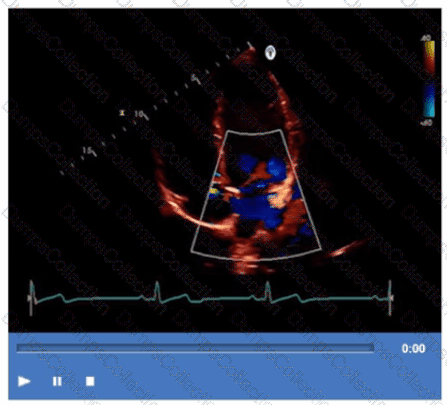

Which finding is shown in this image?